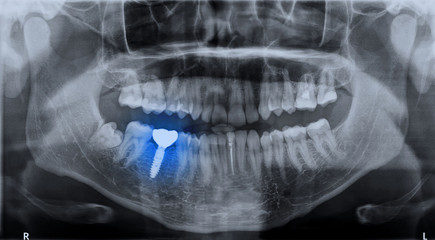

디지털 가이드 임플란트는 3D CT 스캔과 특수 소프트웨어를 사용하여 정확한 임플란트 위치를 계획하고 시술하는 방법입니다. 이 기술은 높은 정확도로 합병증 위험을 감소시키고, 시술 시간을 최대 50%까지 단축시킬 수 있으며, 덜 침습적인 시술로 회복 기간을 단축시킵니다.

비용 효율성 측면에서, 초기 비용은 일반 임플란트 대비 20-30% 높을 수 있지만, 정확한 시술로 인한 합병증 감소와 재시술 필요성 감소로 장기적으로 10-15% 비용 절감이 가능합니다.